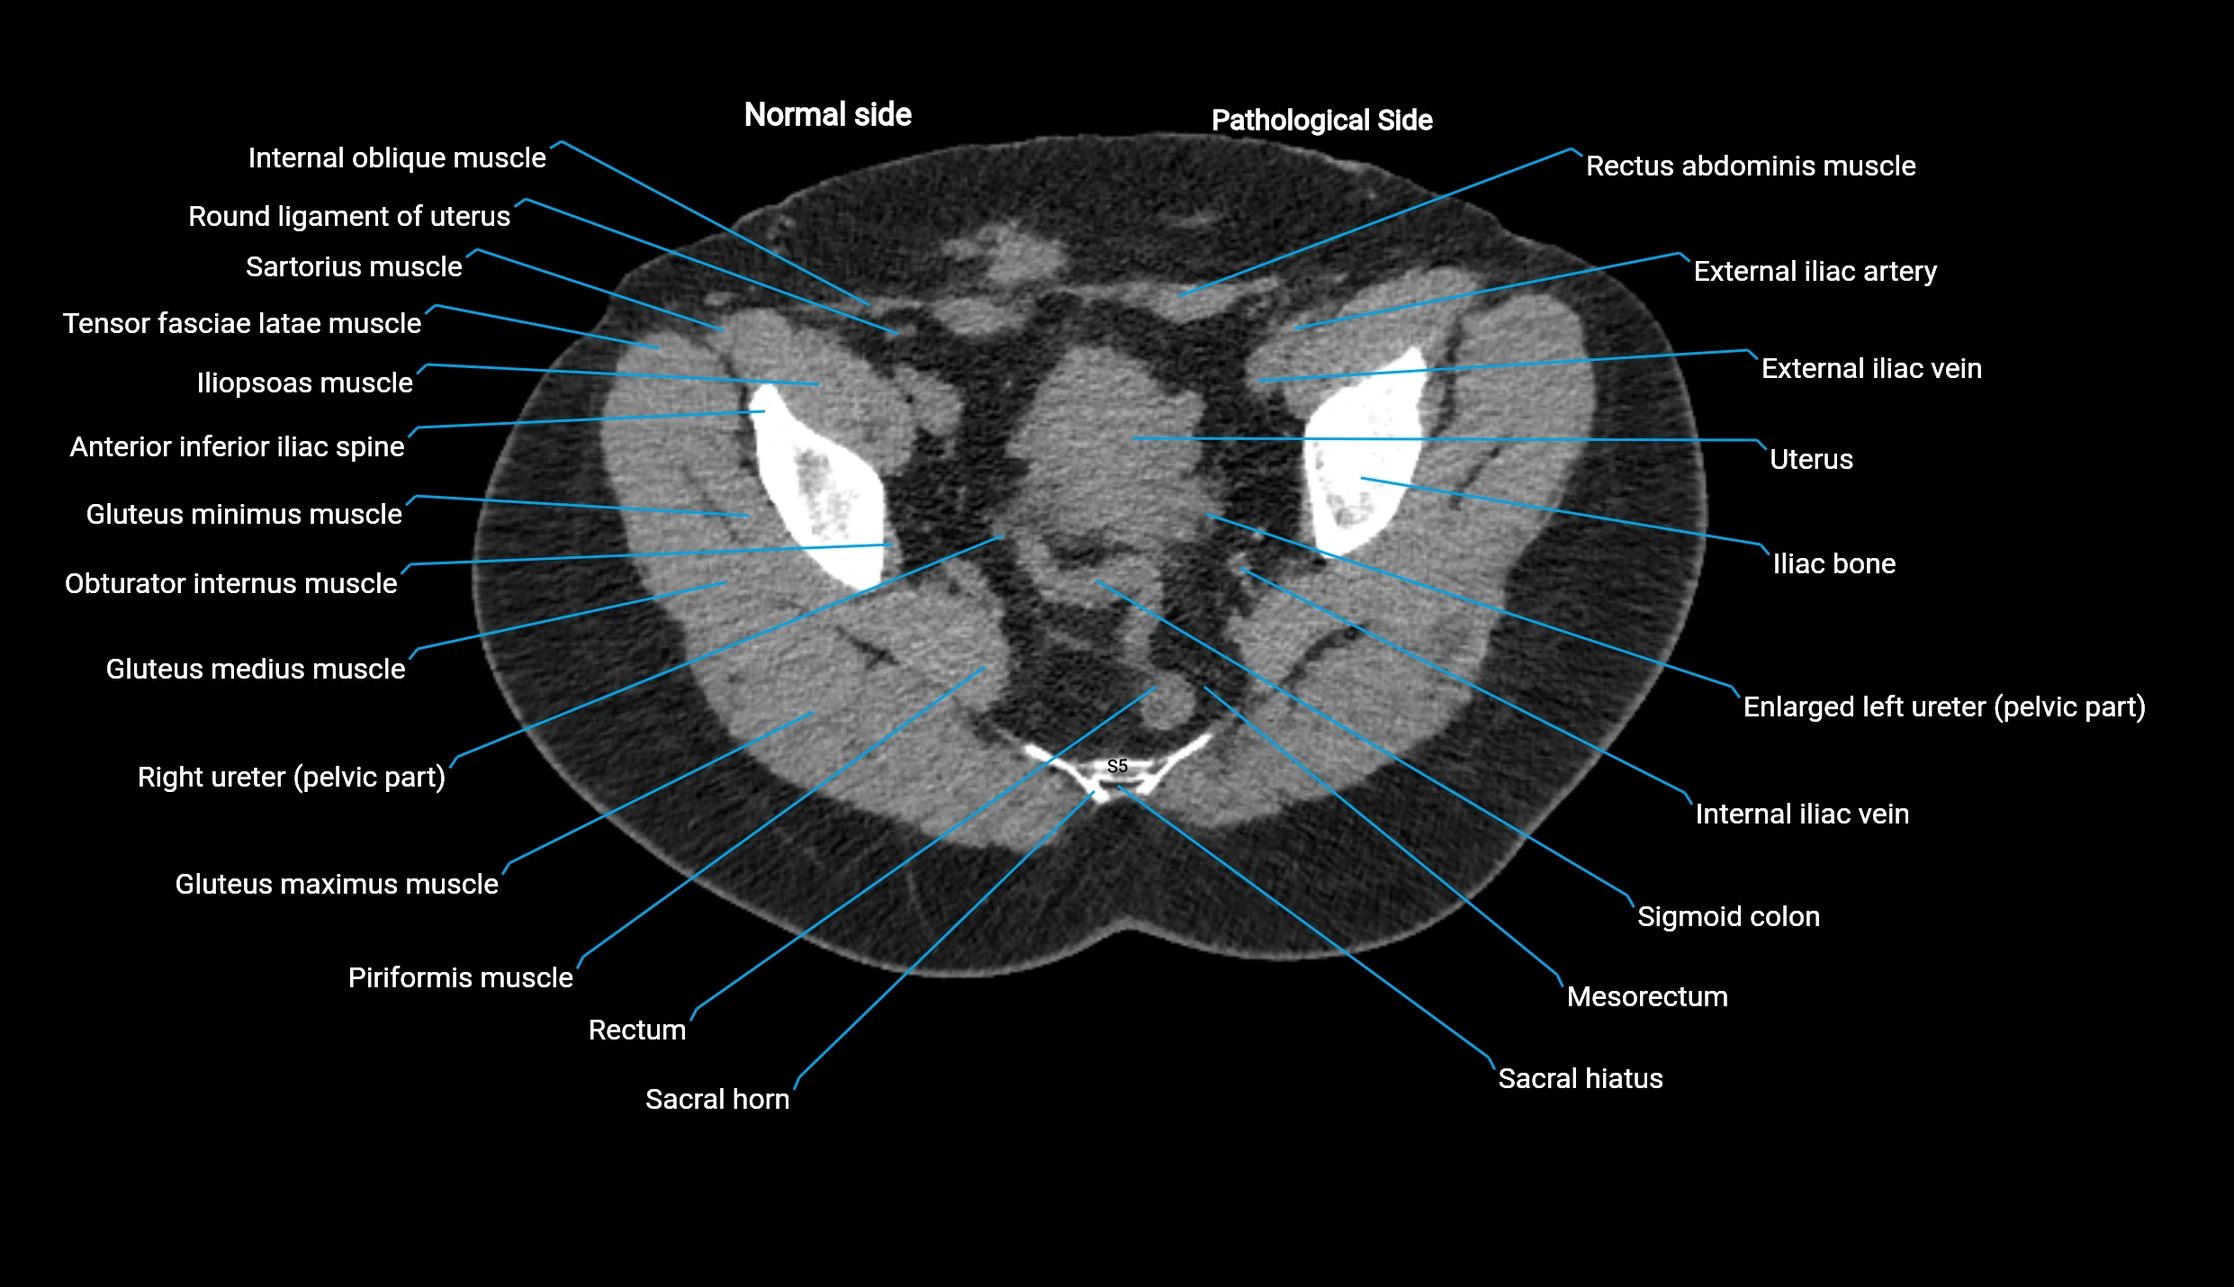

CT image

image